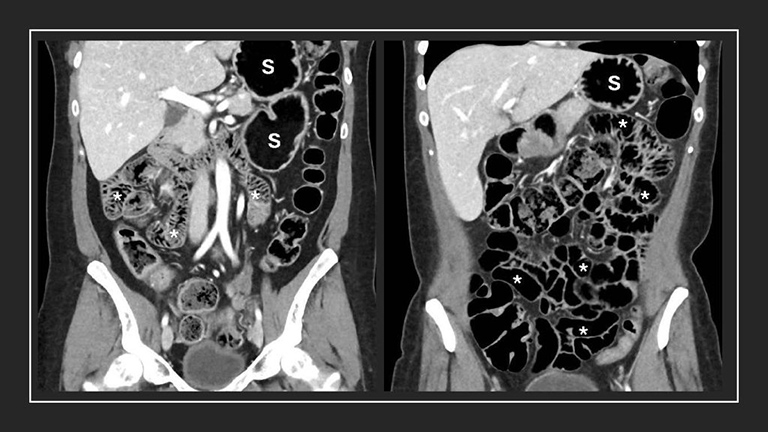

In a new pilot feasibility study, researchers from the University of Washington School of Medicine, the Mayo Clinic, the University of California San Francisco, and Nextrast Inc. found that a new imaging oral agent, also known as a "contrast agent," helps radiologists better see bowel structures and disease in CT imaging when compared with the current oral contrast agents.

In their paper, the authors report findings that suggest this new agent significantly improves visualization of inflammatory bowel disease (IBD) or cancer within the abdomen, and may provide earlier and more confident diagnoses.

The study compared CT scans of 32 patients with the dark borosilicate oral contrast agent and scans with conventional water or iodine-based oral contrast agents, to look at anatomical structures and disease presence.

Evaluators identified clinically relevant findings in seven patients that were not detected using the standard contrast.

"We carefully designed this new class of oral contrast agent to overcome many of the diagnostic shortcomings of existing contrast agents for a broad range of diseases," said Dr. Benjamin Yeh, a study coauthor and radiologist at the University of California at San Francisco. He also is a cofounder of Nextrast, which created the new agent. "The clinical Phase 2 results confirm that our dark agent can reveal previously impossible-to-detect findings, including very small bowel tumors and subtle inflammatory conditions that are often missed with conventional agents at CT."